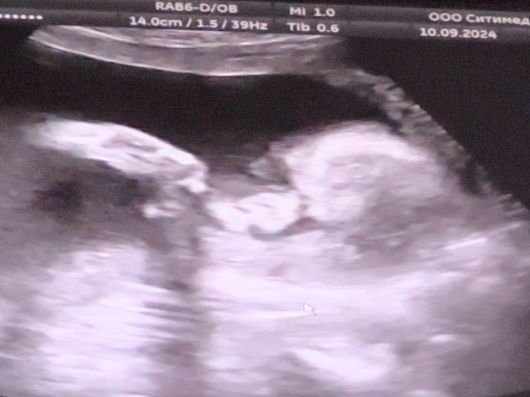

23/4 Нед узи

УЗИ, КТГ, доплерЗа последние 3 нед нисколько не набрала, ну, мне дай повод по переживать … уже придумала СЗРП ( со вторым ставили по этой же причине и доп узи назначали, но по узи всё ок было), решила сделать узи и посмотреть как вырос малыш.

Всё хорошо тьфу-тьфу три раза

638 гр ЧСС 136, шустрый парень